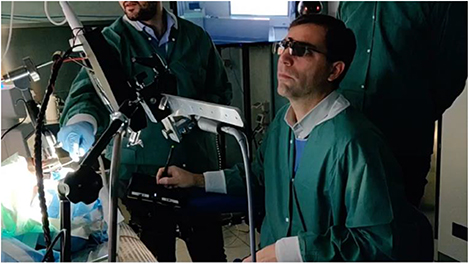

VR, telepresence, and telesurgery: Around the time of the first developments in MIS, NASA was studying options for providing medical care to astronauts. Their research teams were particularly interested in using emerging concepts in virtual reality (VR), haptics, and telepresence. Teams within the US Army (Satava 2002) became aware of this work and were interested in the possibility of decreasing battlefield mortality by bringing the surgeon and operating theatre closer to the wounded soldier (figure 5.11).

Figure 5.11. VR/AR, advanced user interfaces and telecommunications, and robot technology combine to create an enhanced surgical experience.

Tele and remote surgery (Choi et al 2018)

Telesurgery allows a surgeon to operate on (or be virtually present with) a remote patient, by using a robotic surgical system at the patient's site. This involves the use of teleoperation technologies that use real-time, bidirectional information flow: surgical commands must be sent (in real time) to the remote robot, and everything that is happening in the surgical/patient site must be immediately perceived by the surgeon, through visual, auditory, and on occasion haptic feedback. This separation of the surgeon and the patient is already common with most current surgical robots (e.g., the Da Vinci Surgical system), with the surgeon sitting at an operating console that is a few metres away from the robot and patient, but connected with a dedicated wired connection. Telesurgery, on the other hand, refers to medium- and long-distance teleoperation with distances measured in kilometers or even thousands of kilometers between the surgeon and the robot/patient. The connection may use wired as well as 'conventional' broadband, a dedicated connection, wireless, or some combination of wired and wireless.

This large separation between the surgeon and surgical robot brings significant medical advantages but also creates many technical challenges, most of which are directly linked to the need to instantaneously transfer, in a safe, secure, and reliable way, massive amounts of data between both ends of the system. Fortunately, advances in data communication, fibre optic broadband, and particularly the increasingly widespread availability of 5G mean that the long-dreamed goal of truly remote telesurgery is now increasingly possible (Acemoglu et al 2020a). This will be explored in the later section on general requirements in Robotics in Tele-Healthcare.